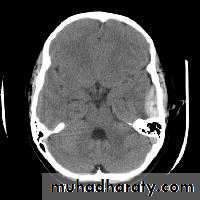

SAH

White sulciOpacified IHF